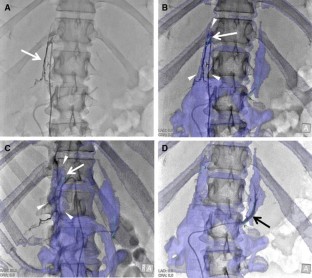

Fig. 2